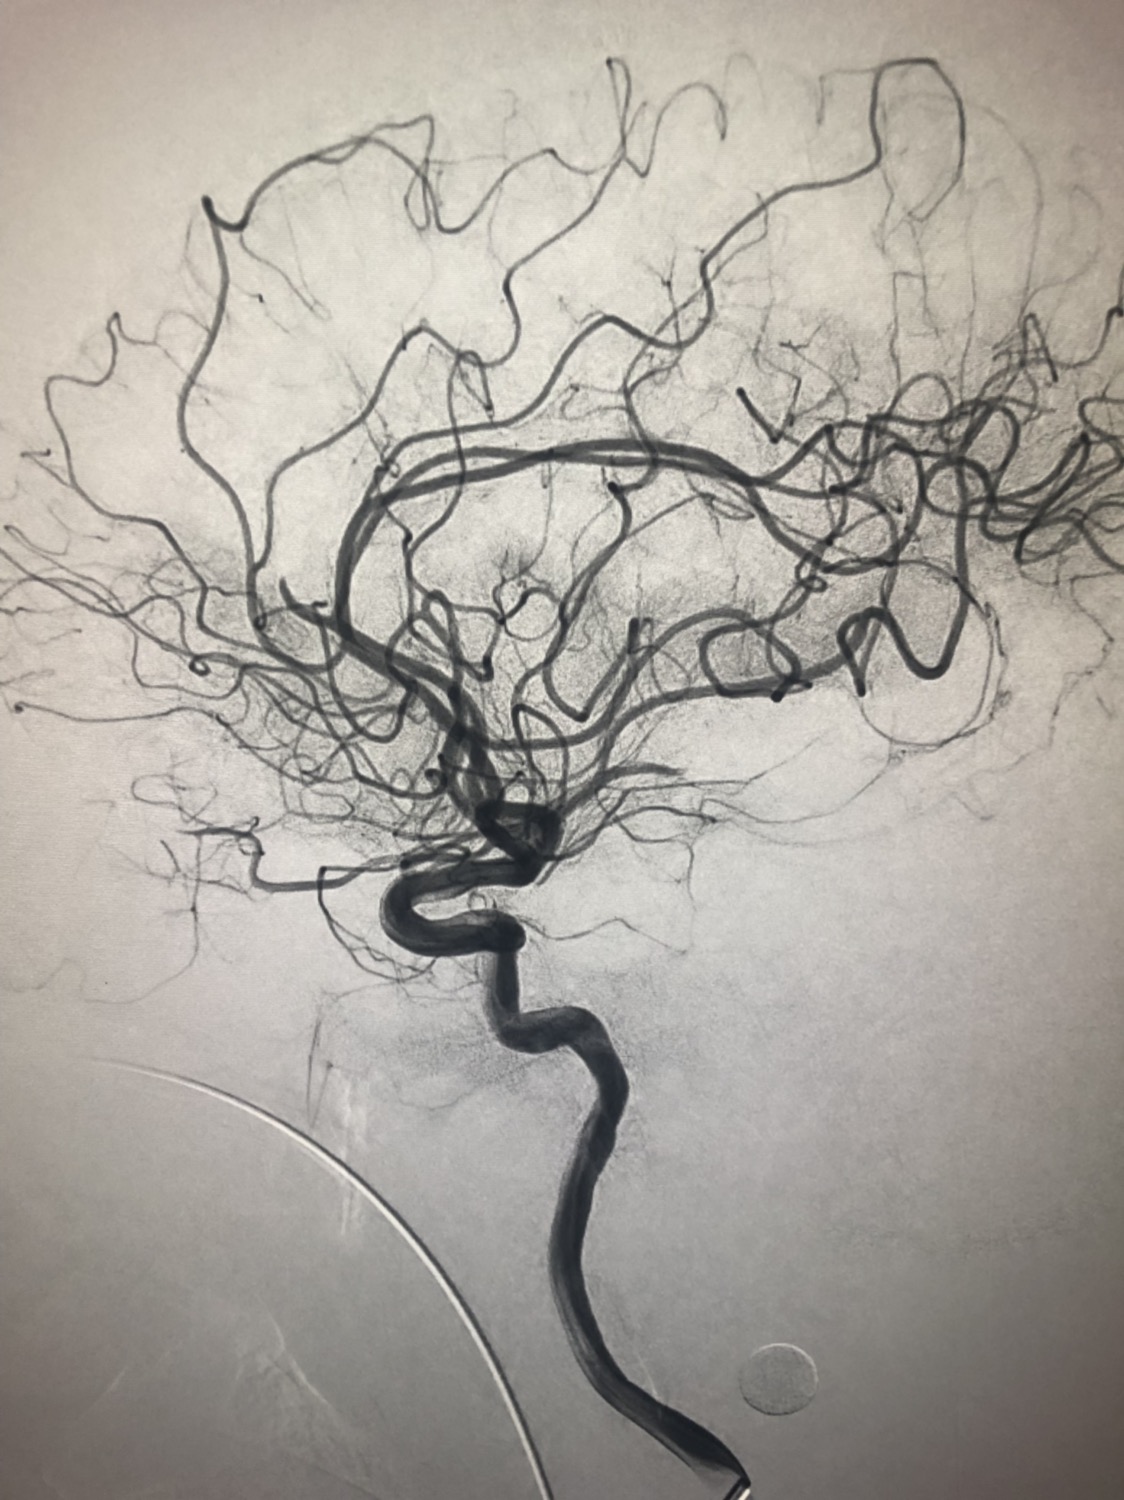

1周前房颤栓塞肱动脉,切开取栓后服用利伐沙班3天。突发偏瘫凝视3小时。上台看M3、A3血栓,国产普威森6f125cm抽吸导管高到位结合尼科3x20mm小支架,结合精细操作,m3和a3的血栓也可以轻松取出。不刺激血管。加造影射线16min两次取栓两个血管再通。

急诊二。zde,f53y。

意识模糊进行性加重8h,基底动脉闭塞,reco取栓再通,貌似动脉硬化,实际血管光滑。造影➕取栓8min。今日团队配合紧密,不到三小时全麻造影取栓带苏醒完成两台取栓。团队棒棒的!南阳市中心医院神经内科脑血管病介入团队